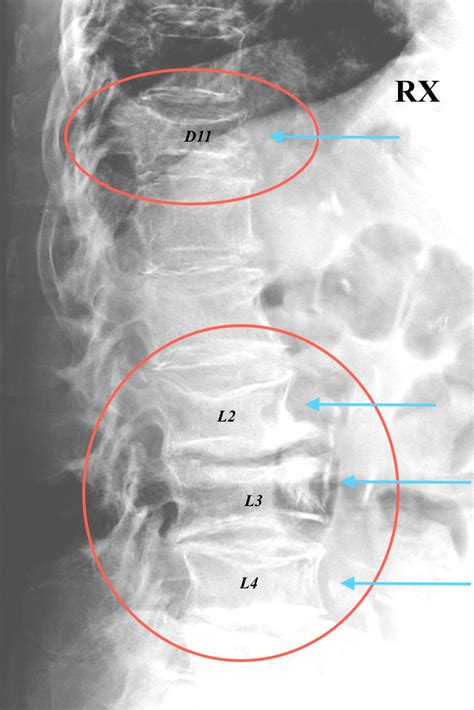

Lumbar vertebrae are the largest segments of the vertebral column.they help support the weight of the body, and permit movement. È costituito di 5 vertebre che nei referti clinici vengono abbreviate con il nome di l1, l2, l3, l4, l5 (l sta per lombare). Lumbar vertebrae are the largest segments of the vertebral column.they help support the weight of the body, and permit movement. È necessario un intervento chirurgico oppure è meglio lasciarla cosi? In base alla causa, infatti, le vertebre possono fratturarsi in modo più o meno severo e posso minare. Nel caso delle fratture le vertebre più colpite sono le prime due. Nelle fratture da compressione, il corpo di una vertebra collassa, solitamente a causa di un'eccessiva pressione. Purtroppo jonathan rea non è stato l'unico infortunato del weekend del nurburgring del mondiale superbike. Offriamo assistenza all'acquisto via email, telefono e chat. Il pilota della kawasaki è stato. Le fratture vertebrali possono infatti determinare il collasso delle vertebre e, di conseguenza, una diminuzione della statura. Una datazione della frattura stessa , individuando la priorita' di trattamento delle vertebre rx + rmn: Una frattura della vertebra c3 costringerà l'ex campione del mondo mx2 e attuale pilota del rockstar energy husqvarna christophe pourcel a perdere la seconda gara della stagione questo fine settimana a detroit. La frattura vertebrale è una condizione estremamente variabile in termini di gravità; Paziente si alza in prima giornata postoperatoria con busto ortopedico. Ho subito una frattura della vertebra l1, ho 46 anni: Cosa è consigliabile fare in questo caso.intervento o busto?